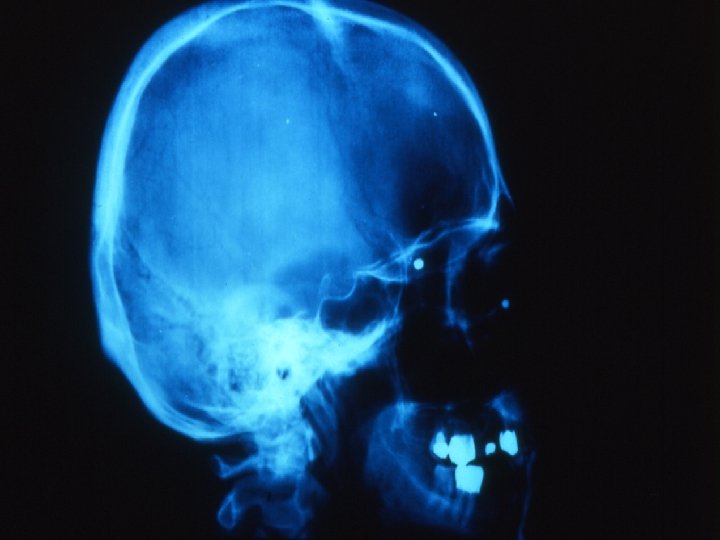

Traumatologie et Brûlures oculaires 3 -Contusion ouverte du globe oculaire Plaie perforante sans CE L’importance des lésions dépend de la taille de l’agent vulnérant, de sa trajectoire dans le globe, de la vitesse à laquelle il arrive sur l’œil Interrogatoire RX ou scanner au moindre doute de CE

Traumatologie et Brûlures oculaires 3 -Contusion ouverte du globe oculaire CEIO Le doute doit être constant Déterminer la nature du CE, sa trajectoire, risque de contamination( végétal, fer rouillé. . )

Traumatologie et Brûlures oculaires 3 -Contusion ouverte du globe oculaire SCANNER , RX standard dans toutes les positions du globe +/- écho. B Dés la moindre suspicion de CE